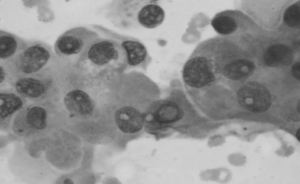

The slides will be sent for analysis under a microscope, and the results usually take a few days to a week.

What are the possible results of the thyroid biopsy?

The results of thyroid FNAC categorize into these three groups:

Likely malignant or cancerous: If the results indicate a high likelihood of malignancy, your surgeon will discuss with you the role of surgery and further treatment options.

Likely benign or non-cancerous: If the results suggest a low likelihood of cancer, your surgeon will likely advise you to monitor the thyroid nodule with a repeat ultrasound in 6 to 12 months. Although the risk of cancer is low, there is still a possibility of sampling error.

Inconclusive: In cases where the results are inconclusive, your surgeon may ask you to repeat the FNAC in 2 to 3 months for a more definitive result.